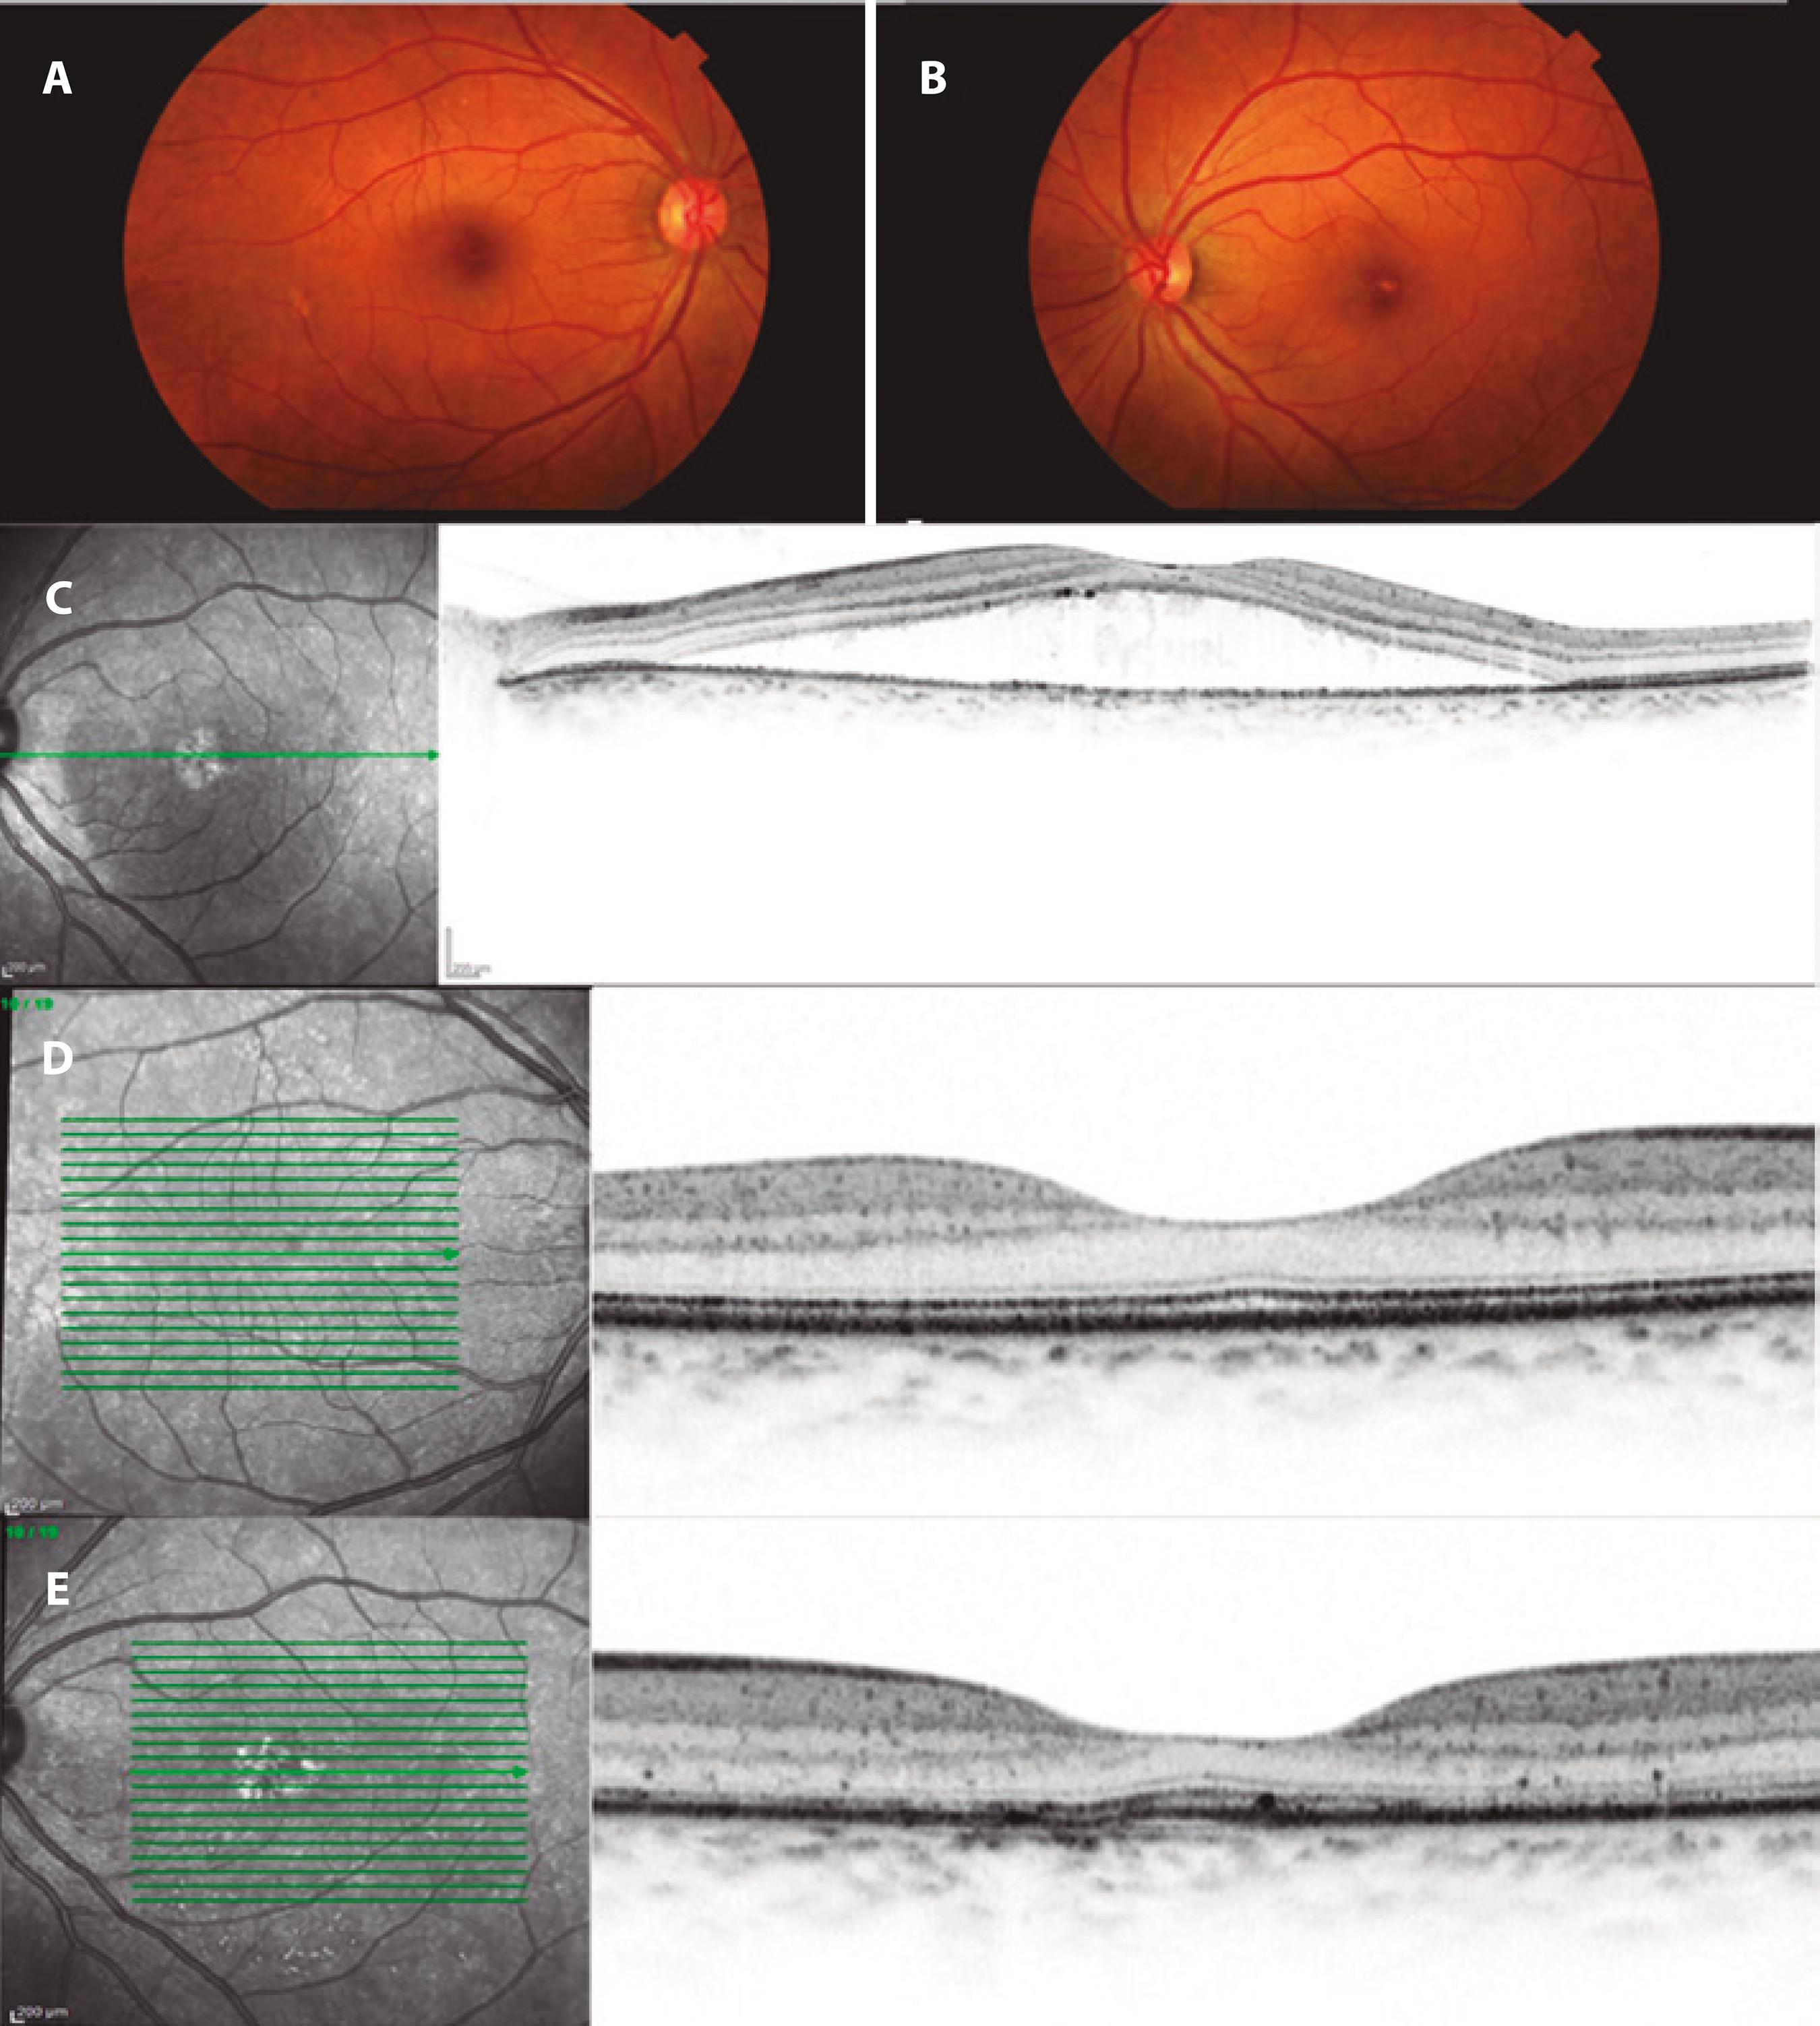

A 47-year-old white woman was seen at the Retina and Vitreous Sector of our hospital in 2012 with symptoms of metamorphopsia and central scotoma in the left eye (oculus sinister ; OS). She had no comorbidities, but reported that she was going through a period of intense emotional stress at the time. Her best-corrected visual acuity (BCVA) was 20/20 for the right eye (oculus dexter , OD; +0.5 D, sphere); by contrast, the BCVA for OS was 20/80 (+0.75 D, sphere). OCT revealed serous retinal detachment in OS (Figure 1), so a diagnosis of CSC was made and the patient's condition was observed. After three months of persistent signs and symptoms, we then started therapy with 250 mg acetazolamide tablets to be taken orally every 8 h for 20 days, and applied focal laser to the OS macular region using a PUREPOINT® Laser (Alcon, USA) set to 100 mW, 50 ms duration, and 33 firings. One month after treatment, clinical improvement was observed, and resolution of serous detachment was confirmed by OCT.

Figure 1 Retinography in OD (A) and OS (B). Yellowish lesions can be seen in the foveal topography of OS. The OCT of OS for the new case (C) shows separation of the photoreceptor layer of the RPE by foveal topography. A recent OCT of OD (D) is normal and in OS (E) there are marks of focal laser in the inferior macular area (infrared) and irregularities of the outer limiting membrane and Bruch/RPE complex in the selected section. OCT= optical coherence tomography; OD= oculus dexter; OS= oculus sinister; RPE= retinal pigment epithelium.

Although the patient suffered no new episodes during follow up, she continued to complain of diminished visual acuity in OS. Objectively, her BCVA was 20/20 in OD (+1.5 D sphere) and 20/25 in OS (+1.0 D sphere). Biomicroscopy revealed transparent corneas, trophic irises, transparent crystalline lenses, and intraocular pressures of 12 mmHg in both eyes. Posterior pole fundoscopy was also within normal limits in OD, but macular topography showed some areas with white and yellowish spots in OS (Figure 1). Therefore, OCT was done. This showed a normal OD with preserved foveal depression, an intact inner layer, and an intact outer layer. Although foveal depression was preserved, and the inner and outer layers were intact in OS, there were some irregular areas on the outer limiting membrane, as well as discrete elevations in both the RPE and Bruch's membrane (Figure 1). In OS, the laser marks in the macular and inferior macular regions were also evident in infrared.